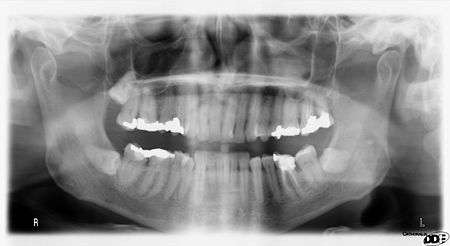

A dental panoramic radiograph, showing the maxilla and mandible, all the teeth including the "wisdom teeth," the frontal and maxillary sinuses, the nasal cavity and the temporomandibular joint and other near by head and neck anatomy. | |

A panoramic radiograph is a panoramic scanning dental X-ray of the upper and lower jaw. It shows a two-dimensional view of a half-circle from ear to ear. Panoramic radiography is a form of tomography; thus, images of multiple planes are taken to make up the composite panoramic image, where the maxilla and mandible are in the focal trough and the structures that are superficial and deep to the trough are blurred.